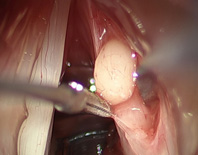

除了傳統聲帶手術,直接將病灶切除的操作方法外,近年來,逐漸發展出聲帶顯微皮瓣手術的新技法,手術中保留聲帶表皮(皮瓣)完整,以精細長柄器械移除深層病灶後(如:圖一、圖二),將皮瓣包覆住聲帶傷口,以恢復聲帶平整的外觀。

圖二、顯微皮瓣手術移除聲帶囊腫